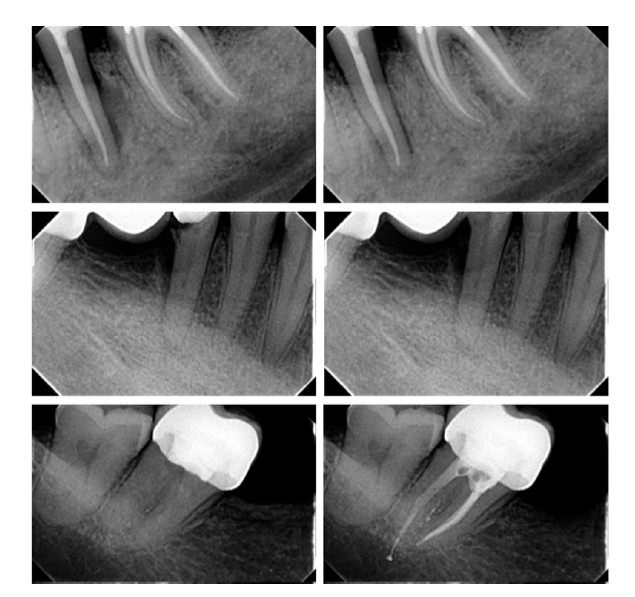

Detección de manipulaciones radiográficas en Endodoncia: la inteligencia artificial en la lucha contra el fraude radiográfico